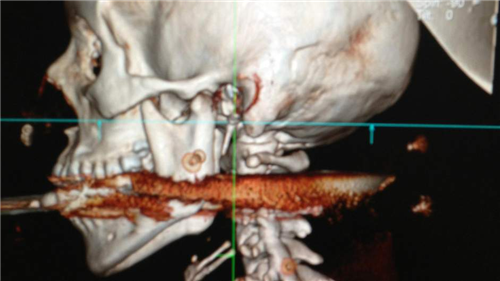

លើសពីនេះ បើយោងតាមសម្តីមន្រ្តីផ្លូវការមកពីទីក្រុង Rio de Janeiro បានគូសបញ្ជាក់អោយដឹងថា ករណីគ្រោះថ្នាក់ចៃដន្យ ដោយអចេនានេះ បានកើតឡើង ខណៈពេលដែលស្វាមីជនរងគ្រោះ បាននឹងកំពុងសម្អាតស្នមួយនេះស្រាប់តែវារាកៃនិងបាញ់ចំមាត់ភរិយារបស់ខ្លួន ធ្លាយដល់បំពង់កតែម្តង។

ភ្លាមៗនោះ ស្រ្តីជាភរិយា វ័យ ២៨ ឆ្នាំ ឈ្មោះ Elisangela Borborema Rosa ត្រូវបានបញ្ជូនទៅកាន់មន្ទីរពេទ្យ ដើម្បីធ្វើការសង្គ្រោះបន្ទាន់ បន្ទាប់ពីមានការវះកាត់ពីសំណាក់ក្រុមវេជ្ជបណ្ឌិត ស្រី្តជាភរិយារូបនោះ ត្រូវបានអះអាងថា បានរួចផុតពីគ្រោះថ្នាក់ ស្របពេលដែល ក្រុមវេជ្ជបណ្ឌិតបានលើកឡើងថា បើសិនណាស្ននោះ មានជម្រៅជ្រៅជាងនេះតែ ១ សង់ទីម៉ែត្រទៀតនោះ ស្ រ្តីរូបនេះពិតជាមិនមានឧកាសក្នុងការរស់រានមានជីវិតនោះទេ នាងពិតជាសំណាងហួស។